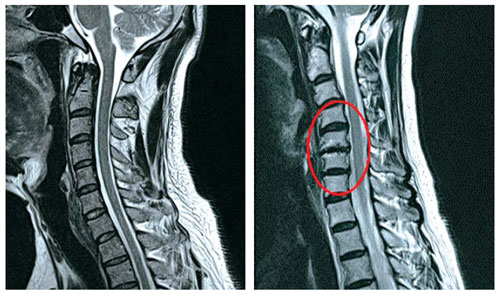

목디스크란 목뼈 사이에 있는 디스크가 손상되어 신경을 압박하는 질환을 의미합니다. 디스크는 젤리와 같은 수핵과 섬유륜으로 구성되어 있습니다. 섬유륜이 손상되면 수핵이 밖으로 밀려나와 신경을 압박하게 됩니다.